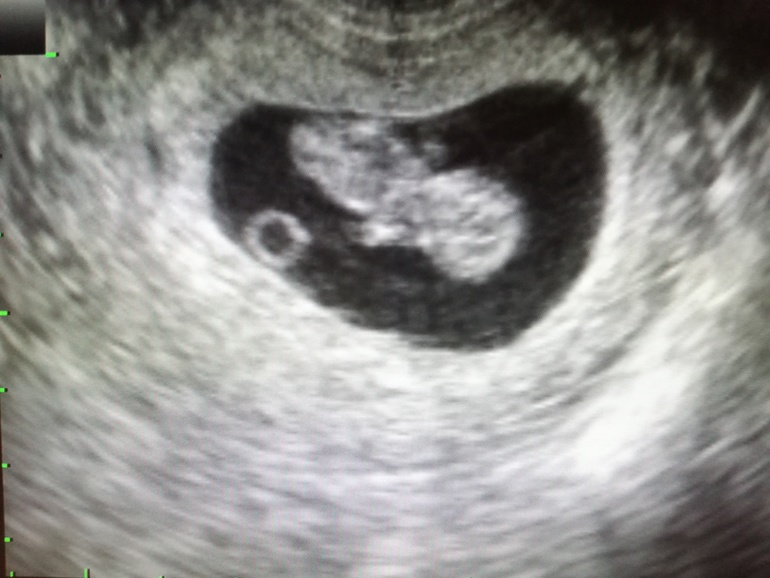

9+5 и мое узи. Хорионит?!

Это типа увеличенный хорион, что ли? Толщина их не устроила?

Типа да, должно быть 10

Тогда могу сказать, что поводов для переживаний нет. На вашем сроке толщина хориона вообще не показательна и увеличение незначительное. Имеет смысл провериться на инфекции, имеет смысл сдать лейкоциты, тк толстеет хорион(будущая плацента), для того, чтобы защитить малыша от инфекций и тд. Если назначит врач. У меня всю беременность увеличенная плацента, утолщённая. С 13 недель толщина 32 мм. Это повод для дополнительного наблюдения, справляется ли плацента с функциями питания плода, толстая плацента не лечится. Моя - справляется. Уверена, что ваша - тоже 💪